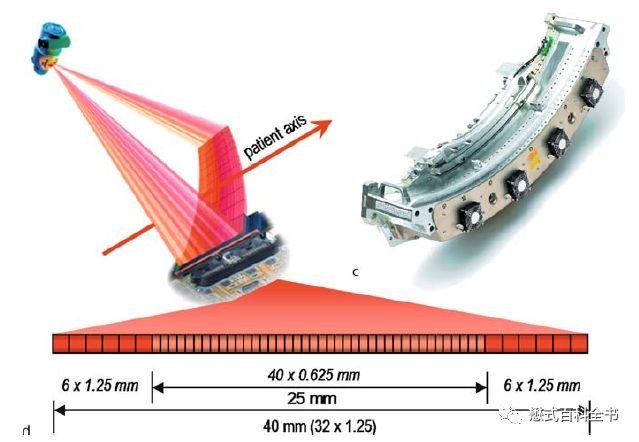

“排”是指CT探测器在Z轴方向的物理排列数目,简单来讲就是有多少排(个)探测器,就是多少排CT,这个指标主要是反映CT硬件结构。可以说排是一个硬件性参数。所谓硬件性参数就是直接可以在硬件(实体)中反映出来的,比如64排,那么可以数出来探测器的阵列数。目前的CT都是多排CT(MDCT),即Multi-detector CT或者可以写成Multi-row CT或者Multiple detector row CT。

“层”是指CT数据采集系统(Data Acquisition System, DAS)同步获得图像的能力,简单的说就是同步采集图像的DAS通道数目或机架旋转时同步采集图像的层数,这个指标主要是反映CT扫描的功能。可以说层是一个功能性参数。所谓功能性参数是指要通过图像性能来反映的,不能直接通过实体显示。有多少层CT就代表扫描一圈能够同步获得多少幅图像。比如,我们常说的16层CT、64层CT,就是表示扫描一圈能够获得16层图像、64层图像。目前的CT基本上都是多层CT(MSCT),即Multi-Slice CT或Multi-slice spiral CT或Multislice CT。

前面讲了“排”代表探测器的阵列数,一般来说排越多,探测器宽度越宽,一次扫描完成的宽度越大,一次扫描得到的图像也越多。但是由于探测器的物理排布,组合方式及设计理念的不同,“排”数相同的CT得到的“层”数可能并不一样。

举个例子,如果每排探测器一次采集可以获得2幅图像,那么一排实际上对应的是两层。比如,某某机器的64层CT,实际上探测器是32排,每排出2幅图,一次采集可以获得64幅图像,所以该CT也可以叫做64层CT,也可以叫做32排CT。

在MSCT多层CT技术中,DAS控制着数据的采集及传输。利用DAS电子开关对受X线激发的多排探测器陈列的不同组合,可以进行不同层厚图像的采集。但是同步采集图像的层数仍然受到DAS通道数目的限制。也就是说,DAS是真正的决定同步多层采集图像的能力,与容积成像能力相关的应该是DAS通道数目,即“层”的数目。因此,层的叫法应该更准确。“排”的数目多少只决定对不同采集层厚的组合能力,与CT同步采集层数并没有直接的关系。因此,“层”更能精确地评价CT机器的扫描性能,也更便于CT使用者的理解。

第二次飞越是由单层螺旋CT发展为多层螺旋CT。多层螺旋CT是指在单层螺旋CT的基础上,增加了探测器在Z轴方向上的-排列数目,这样可以使X线管旋转一周,完成多个层面(断面)的数据采集。相比于单层CT,多层螺旋CT的主要优势在于扫描速度的大幅度提高。扫描速度提高以后,我们可以做很多新的项目,如一些呼吸运动器官的扫描得以实现。另外,由于Z轴(即层面方向)的探测器数目增加,使CT扫描的层厚得以更薄,提高了Z轴方向的空间分辨率或者层间分辨率,这样可以使各项同性成像成为可能。